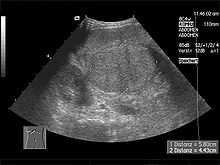

Im Ultraschall stellt sich die Leber inhomogen dar. Der Leberrand ist wellig, die Binnengefäße sind rarefiziert. Der Lobus caudatus kann vergrößert sein. Sehr gut können mit dem Ultraschall ein Aszites und eine Milzvergrößerung (Splenomegalie) erkannt werden. Eine verbesserte Form der Sonographie stellt der sogenannte Fibroscan, auch bekannt als transiente Elastografie, dar. Hiermit kann die Fibrosierung, also der Bindegewebsumbau, der Leber ermittelt werden, was ein sehr zuverlässiges Ergebnis zur Diagnosestellung liefert und zukünftig die Leberbiopsie (s.u.) ersetzen könnte. Mit der Farbduplexsonographie lässt sich in den Lebervenen eine verminderte Elastizität der Leber, in der Pfortader ein verminderter Fluss sowie in der Leberarterie ein erhöhter peripherer Widerstand messen.